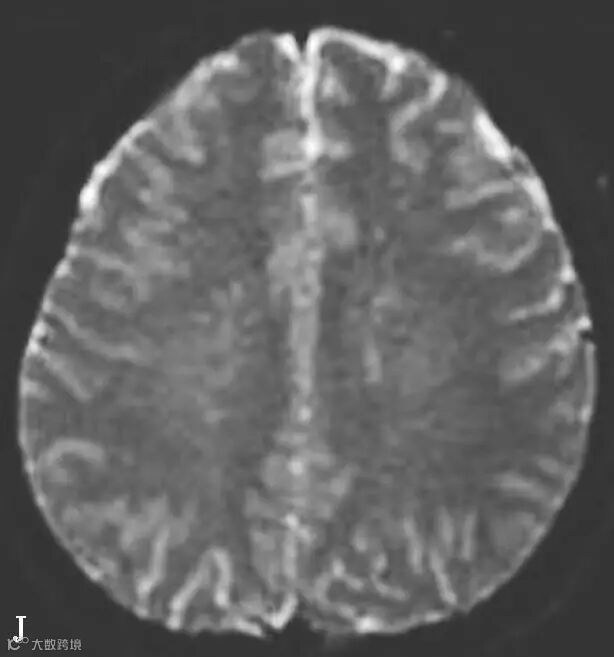

图6-11-2 弥漫性轴索损伤

男,36岁,外伤后2天。A~J(A、B.T2WI,C、D.T1WI,E、F.T2WI-FLAIR,G、H.DWI,I、J.ADC图):双侧额叶、半卵圆中心及胼胝体压部可见多发斑点状等T1稍长T2信号,边缘不清,FLAIR及DWI呈高信号,ADC图病灶信号减低 。